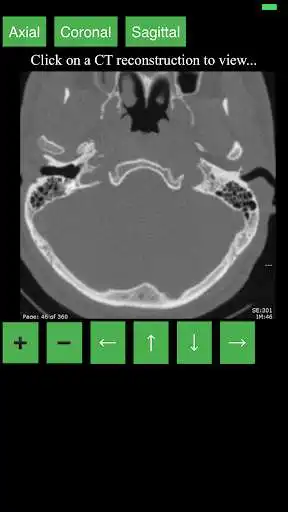

This app provides a dynamic and interactive method of viewing cross-sectional human anatomy on computed tomography (CT). The information contained in this app cannot be guaranteed for completeness and accuracy.

- Labeling of anatomical parts

- 3D Anatomic localization